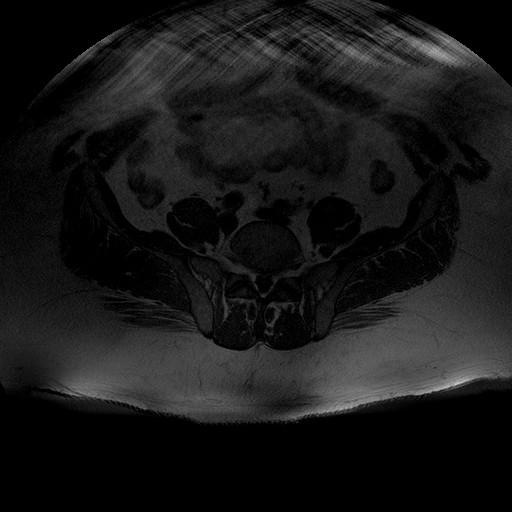

Esami: RMN BACINO

T1W_TSE

Evidenti e simmetriche alterazioni osteofitosiche in regione coxo femorale con riduzione delle rime articolari. Degenerazione completa del cercine glenoideo. Non attuali segni di versamento articolare. Non segni di edema osseo che escludono attuale algodistrofia od osteonecrosi. Lieve e simmetrica riduzione del trofismo della muscolatura glutea.